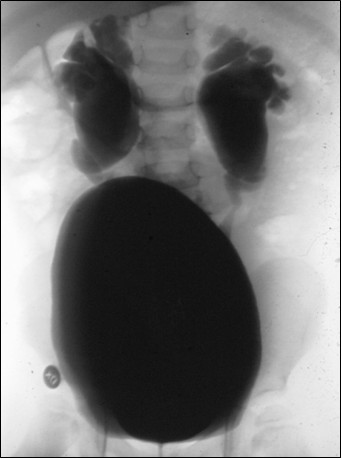

U 9-miesięcznego chłopca z zakażeniem układu moczowego w wywiadzie, wykonano cystografię mikcyjną (patrz poniższe zdjęcie). Jakie badania należy wykonać w następnej kolejności?